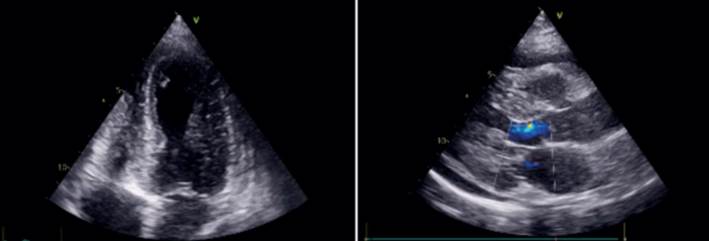

La radiografía de tórax mostró escaso edema intersticio-alveolar difuso. Se realizó ecocardiograma transtorácico (ETT) en el que se observó un remodelado concéntrico del ventrículo izquierdo (VI), hipoquinesia de los segmentos apicales a predominio septal y anterior con una fracción de eyección del VI (FEVI) levemente disminuida (50%) y derrame pericárdico leve (figura 2).

Se realizó un nuevo ETT que mostró aquinesia de todos los segmentos apicales y de los segmentos medios de la pared anterior y septal anterior, FEVI 38%, insuficiencia mitral e insuficiencia tricuspídea moderadas, hipertensión pulmonar (presión sistólica de la arteria pulmonar estimada en 62 mmHg) y derrame pericárdico leve sin repercusión hemodinámica.

En la evolución presentó peoría clínica, con elementos de insuficiencia cardíaca derecha e izquierda. Se realizó control con ETT al cuarto y séptimo día del ingreso, en los que se observó deterioro funcional del VI, con aquinesia apical en todos sus sectores, inferior en todos sus sectores y anterior medio con hipoquinesia lateral, FEVI 28% y aumento del derrame pericárdico. Este fue moderado sin repercusión hemodinámica.

Los hallazgos electrocardiográficos más frecuentes son la taquicardia sinusal y alteraciones inespecíficas del segmento ST y la onda T, así como anormalidades de la conducción y arritmias. En el ecocardiograma puede aparecer disfunción sistólica global o regional y derrame pericárdico. La miocarditis fulminante a menudo se presenta como miocardio engrosado e hipocontráctil, como resultado del edema intersticial y la pérdida de contracción ventricular4.